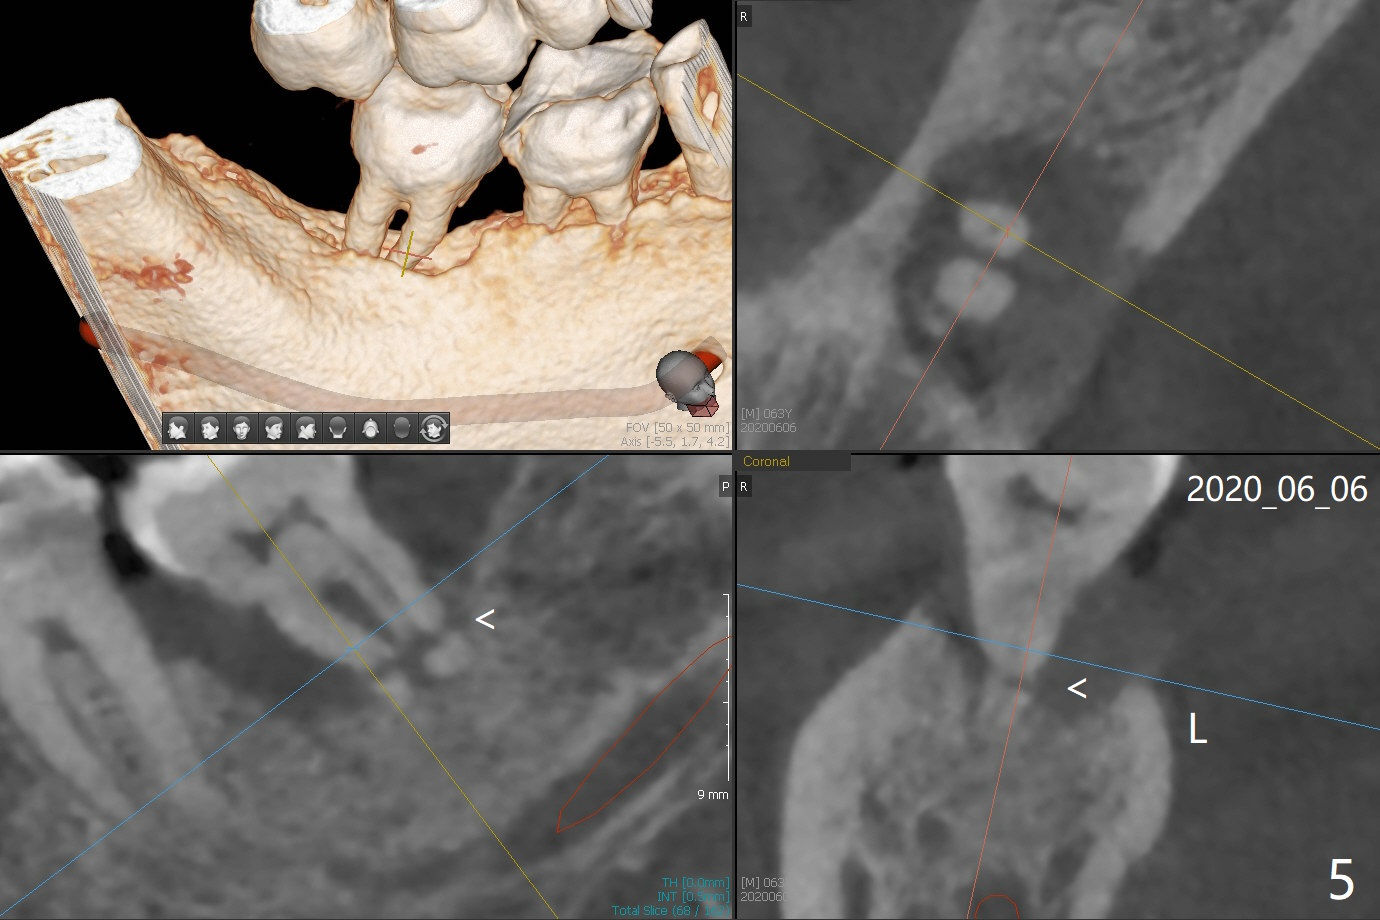

A 60-year-old man has chronic periodontitis, bruxism and malocclusion, e.g., #18 mesiolingual inclination (under occlusal trauma, Fig.1). The lingual pocket is deep with severe bone loss. After extraction, use implant positioner to gauze the size of the socket. Initiate osteotomy as mesial as possible and parallel to the 1st molar (Fig.2,3). Bone density is expected to be high. Prepare soft (1-piece) and hard (IS) tissue-level implants. The tooth remains loose 2 years later, although the patient is asymptomatic (Fig.4). Finally the tooth is symptomatic because of root tip fracture (Fig.5). Use drills with 7.3 mm stop for 4.5 or 5.0x8.5 mm implant free hand (Fig.6). The exposed implant will be covered with sticky bone (PRFx2). Prepare temporary and cemented abutments to hold bone graft in place.